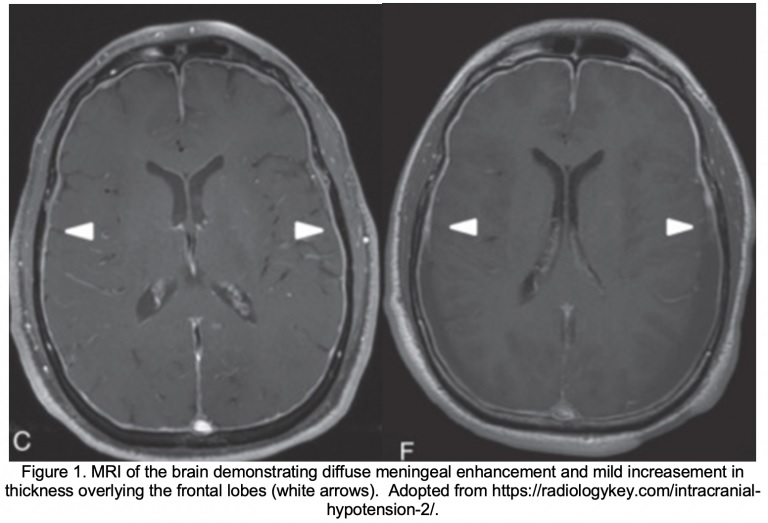

Imagerie par résonance magnétique (IRM) du cerveau . La principale modalité d’imagerie qui serait utile pour obtenir le diagnostic de SIH est une IRM du cerveau avec et sans produit de contraste . L’acronyme SEEPS, qui signifie collections de liquide sous-dural, rehaussement pachyméningé, engorgement veineux, hyperémie hypophysaire et flaccidité cérébrale, sont les principales caractéristiques du SIH observées en IRM.

Parmi ces observations, la plus courante et la plus pathognomonique est un rehaussement pachyméningé uniforme et diffus . En termes simples, cela signifie une amélioration de la dure-mère et de la couche externe de l’arachnoïde après administration d’un produit de contraste pour une IRM du cerveau.

Le patient a subi une tomodensitométrie cérébrale et une CTA qui n’ont montré aucune anomalie intracrânienne aiguë. Une IRM du cerveau a ensuite été obtenue, révélant un rehaussement pachyméningé diffus, un épaississement et un engorgement du sinus veineux dural. Le patient a été admis à l’unité d’observation pour des examens plus approfondis, notamment une IRM T/L de la colonne vertébrale, qui a montré une importante accumulation de liquide péridural, probablement due à une lésion de la gaine de la racine nerveuse T5-T6. Elle a consulté un anesthésiologiste, s’est fait poser un patch sanguin péridural et a pu rentrer chez elle avec la résolution de ses symptômes.